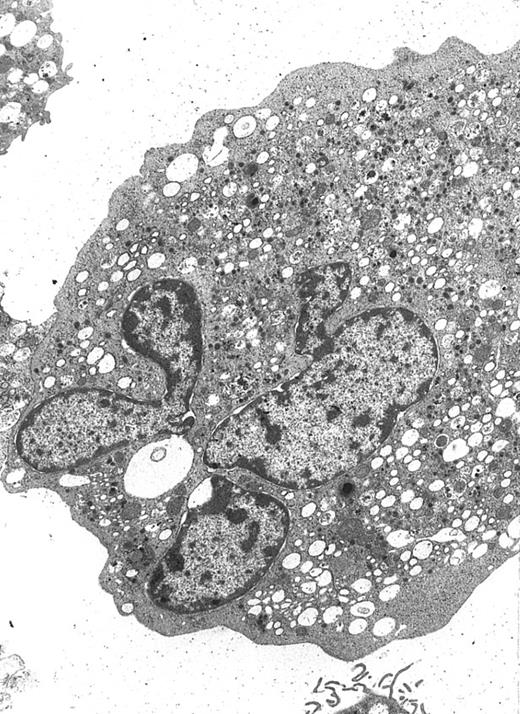

Cytospin preparations of megakaryocytes generated from purified CD34+ cells cultured for 14 days in the presence of MIP-1α, IL-3, IL-6, IL-11, FL, SCF, and MGDF. Most cells displayed a CD61+ phenotype detected by APAAP staining. In (A) cells were treated by BFA and staining was more intense on the cells' surface. Cells in (B) were permeabilized by acetone, and a number of proplatelet structures are visible, together with CD61+ cells with increased ploidy.